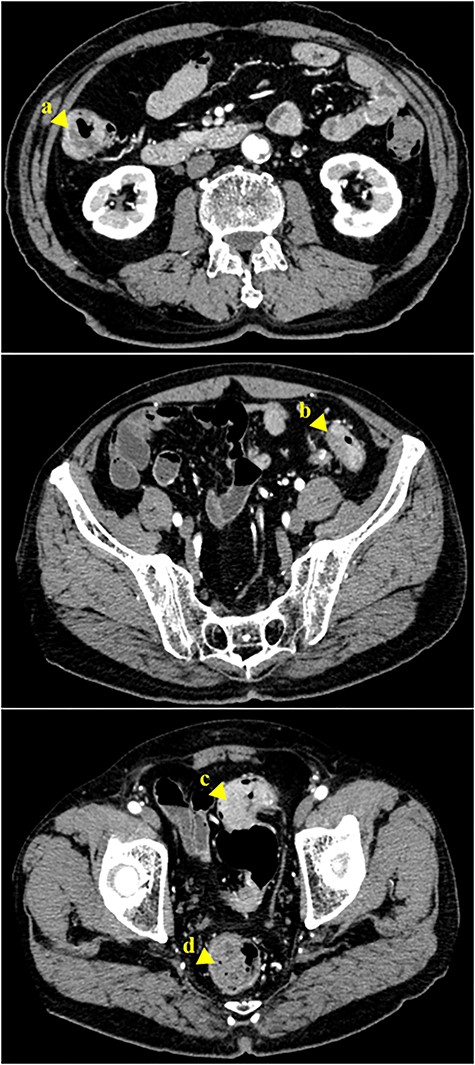

A 70-year-old man who was positive for a blood stool test visited our hospital. Colonoscopy, computed tomography (CT) and barium enema indicated quadruple concurrent locally advanced cancers. The first tumor, with observed lumen stenosis, was located in the ascending colon; the second tumor was located in the descending colon and the third and fourth tumors were located in the sigmoid colon (Fig. 1). CT revealed marked intestinal wall thickness in the ascending, descending and sigmoid colon (Fig. 2). Preoperative precise simulation using 3D angiography was performed to determine adequate lymph node dissection along the arteries feeding the tumors and appropriate resection to avoid anastomotic leakages.

Abdominal CT scan revealing a tumor of the ascending colon (a, arrowhead). A tumor in the descending colon (b, arrowhead), and two tumors in the sigmoid colon are also visible (c, d, arrowhead)